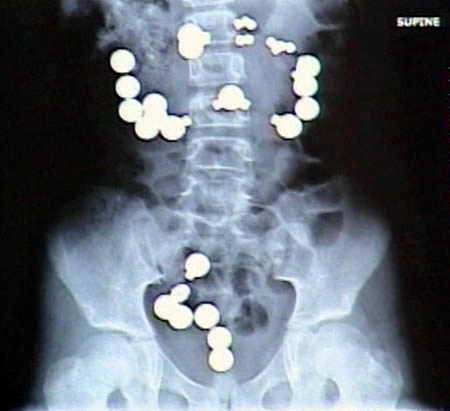

این کودک 8 ساله اهل ایالت ایندیانای ایالات متحده 10 آهن ربا و 20 گلوله فلزی متعلق به یک ست بازی مغناطیسی رو بلعیده!!!!!این آهن رباها و گلوله ها داخل دستگاه گوارش این بچه همدیگر رو جذب کردند و سبب ایجاد 8 سوراخ در روده این کوچولو شدند.خوشبختانه والدینش سریعا بردنش بیمارستان.این بچه بعدا گفته که گلوله ها شبیه آب نبات بودند!!!!!!